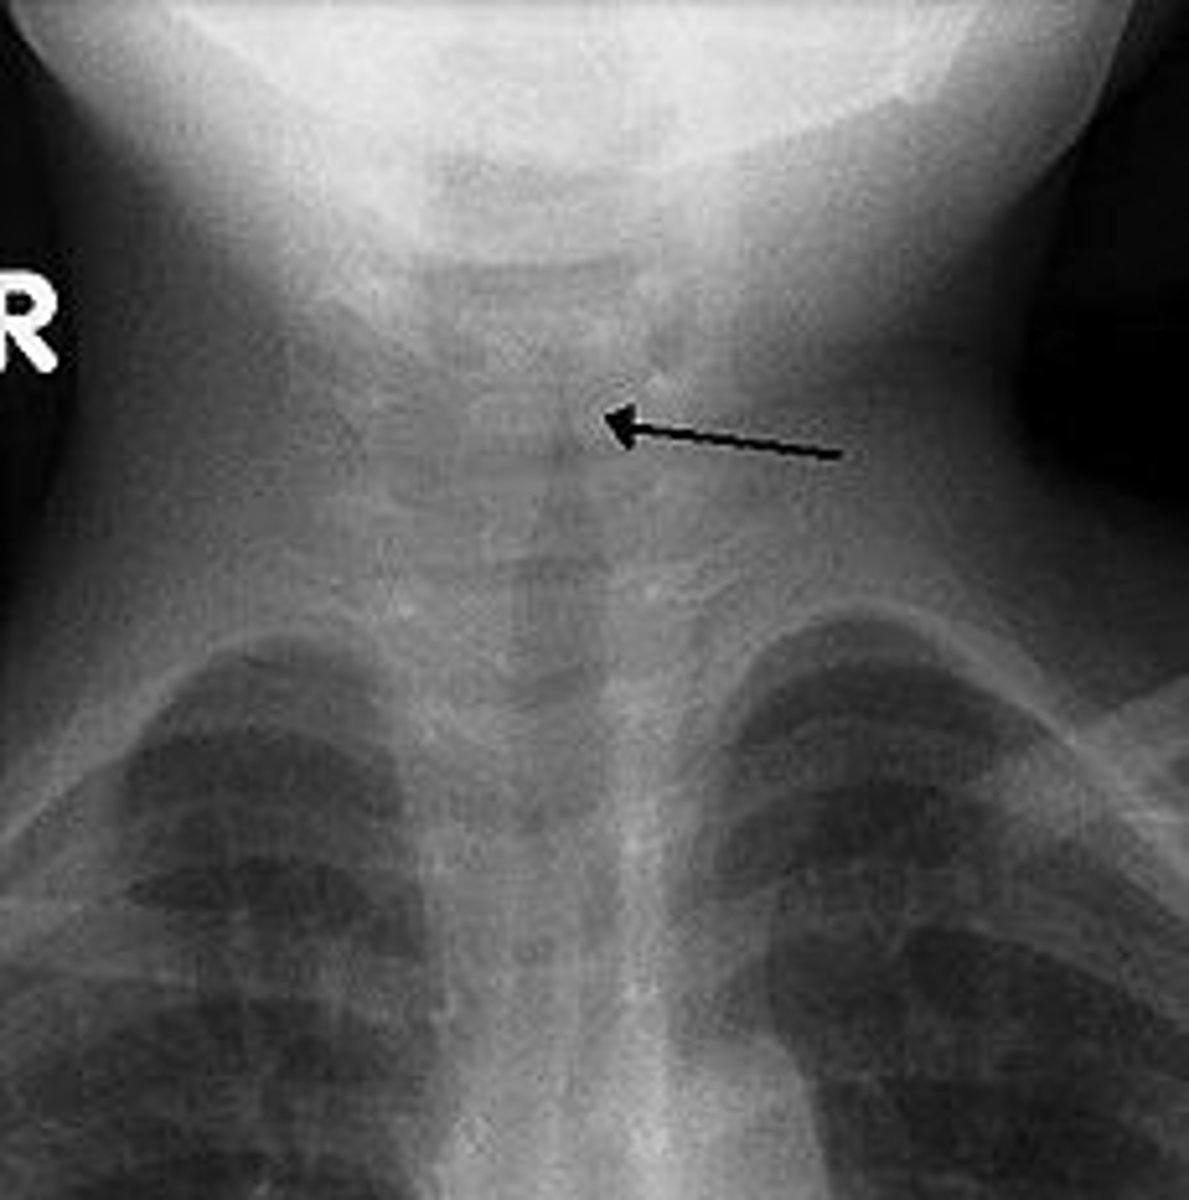

croup

Laryngotracheobronchitis that causes a barking cough, stridor (vibrating noise), hoarseness, and difficulty breathing, which usually occurs at night (parainfluenza)

steeple sign

Subglottic stenosis or narrowing of the opening below the vocal folds is a classic sign of croup.